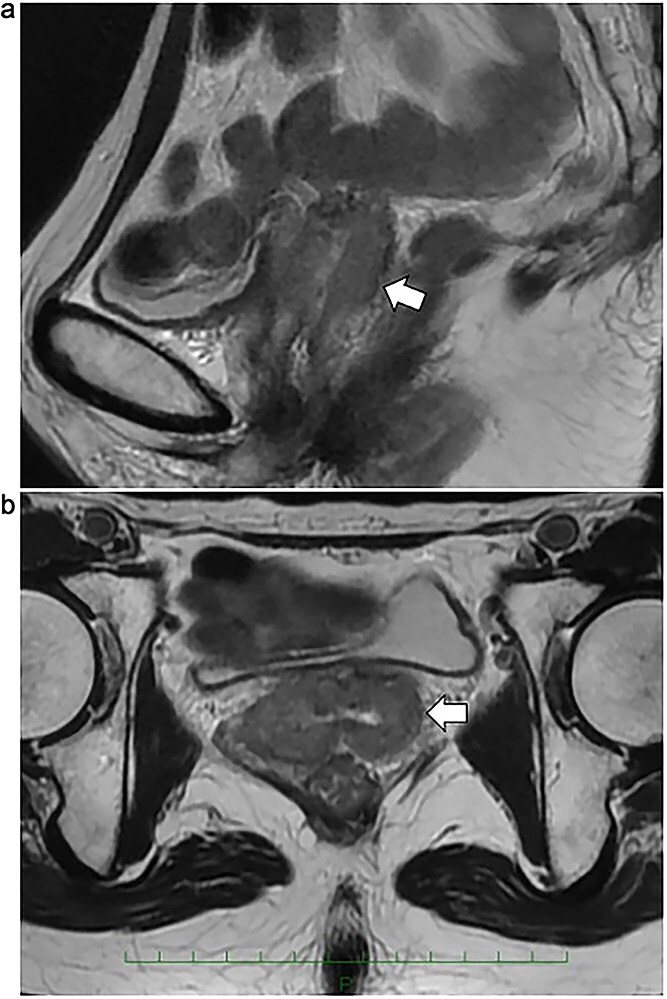

In recurrent gynecologic malignancies following prior pelvic irradiation, definitive radiation therapy is often precluded by cumulative dose constraints to adjacent organs at risk (OARs), and patients may be left with only highly invasive surgical options such as total pelvic exenteration. While some institutions have explored displacement techniques such as artificial ascites or hyaluronic acid gel injection, these approaches are not widely adopted and frequently fail to ensure consistent and stable separation of OARs. We report the first clinical use of Neskeep®, a bioabsorbable polyglycolic acid (PGA) spacer, in high-dose-rate (HDR) brachytherapy for recurrent cervical cancer after prior pelvic radiation. A woman in her 40s with prior hysterectomy and HDR brachytherapy for cervical intraepithelial neoplasia grade III developed vaginal stump recurrence 4 years later. Laparoscopic placement of the PGA spacer was performed to achieve durable displacement of the small bowel, followed by eight fractions of HDR brachytherapy. Hyaluronic acid gel was also injected during each fraction to displace the bladder and rectum. The spacer maintained position and volume throughout treatment without complications. Dose-volume analysis showed a marked reduction in small bowel D₂cc (mean equivalent dose in 2 Gy fractions (EQD₂): 121.6 cGy) compared to the initial treatment (606.0 cGy), while the spacer itself received a mean D₂cc of 690.3 cGy. MRI confirmed complete response at 2 months, with no adverse events observed at that time point. The PGA spacer enabled safe, curative reirradiation in a case that would otherwise be unsuitable for further radiation therapy.